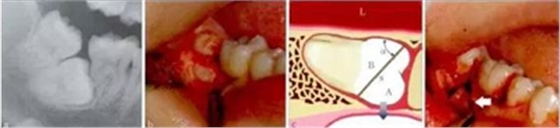

這個(gè)實(shí)際上是最簡(jiǎn)單的運(yùn)動(dòng)力學(xué)原理,物體O受到周圍物體的抱持緊固而不易脫位,為了便于脫位,可以通過切割,人為地形成一個(gè)斜面,而沿著這個(gè)斜面,A將非常容易脫位,斜面越大,內(nèi)摩擦角α越小,阻力越小。而A脫位后,B就失去了周圍組織

的抱持緊固而易于脫位(圖1)。具體操作時(shí),需要根據(jù)操作的可及性,靈活設(shè)計(jì)斜面的方向,必要時(shí)可多次分牙。

圖1 斜面原理。阻生的47已造成46遠(yuǎn)中牙根部分吸收(a),手術(shù)入路較為狹小而受限(b)。為了解除47脫位阻力,對(duì)牙體進(jìn)行分割(c)。將47牙切割成A和B,A部分因斜面(s)的存在可沿藍(lán)色箭頭方向順利脫位,并為B部分的松解創(chuàng)造空間,松解

后的B部分可通過多次分割取出(d)。如此可以盡量減少開窗去骨量,多保留鄰牙頸緣的骨質(zhì)(白色箭頭)。α:內(nèi)摩擦角;L:舌側(cè)。